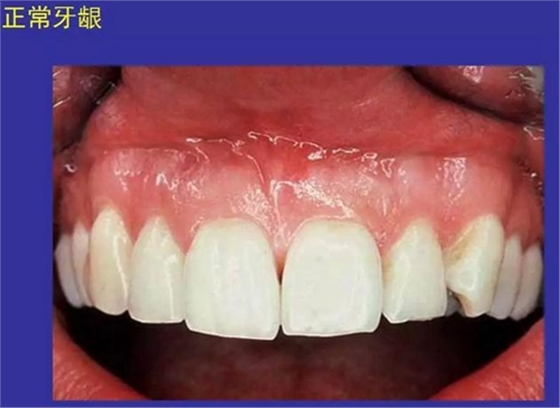

①口腔黏膜(oral mucosa):口腔內(nèi)的濕潤襯里

口腔黏膜感染性疾病及潰瘍類疾病圖示

一、口腔黏膜感染性疾病圖示